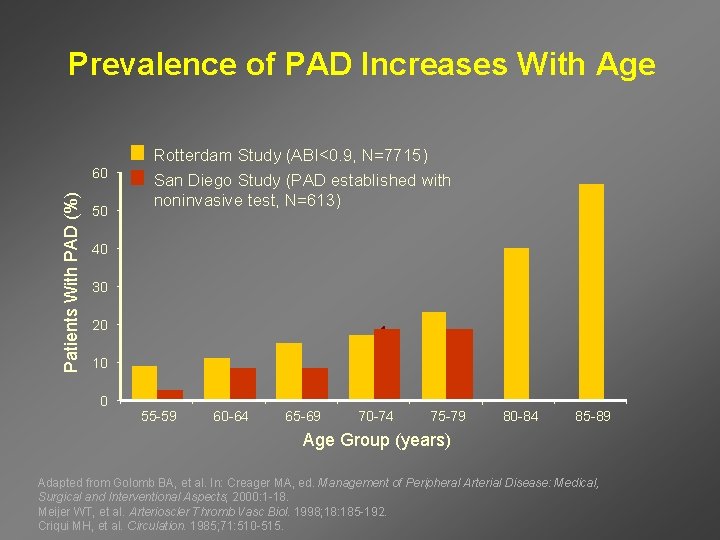

Prevalence of PAD Increases With Age Patients With PAD (%) 60 50 Rotterdam Study (ABI<0. 9, N=7715) San Diego Study (PAD established with noninvasive test, N=613) 40 30 20 10 0 55 -59 60 -64 65 -69 70 -74 75 -79 80 -84 85 -89 Age Group (years) Adapted from Golomb BA, et al. In: Creager MA, ed. Management of Peripheral Arterial Disease: Medical, Surgical and Interventional Aspects; 2000: 1 -18. Meijer WT, et al. Arterioscler Thromb Vasc Biol. 1998; 18: 185 -192. Criqui MH, et al. Circulation. 1985; 71: 510 -515.